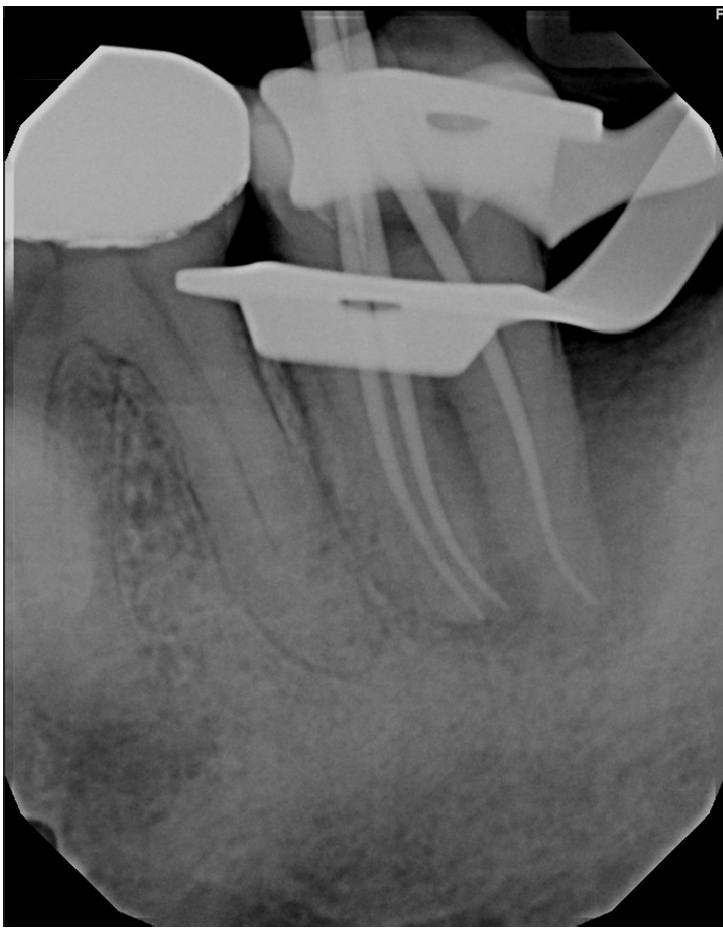

Radiographically, a “J-shaped” lesion was observed along the distal root of #18 (Figure 1), suggestive of a primary endodontic lesion with secondary periodontal involvement. A radiopaque fragment, consistent with a cemental tear, was identified along the distal root surface (Figure 1).

Figure 1.

“J-shaped” lesion observed along the distal root of #18 (yellow arrow). A radiopaque fragment, consistent with a cemental tear, was identified along the distal root surface (red arrow).

Figure 1. “J-shaped” lesion observed along the distal root of #18 (yellow arrow). A radiopaque fragment, consistent with a cemental tear, was identified along the distal root surface (red arrow).